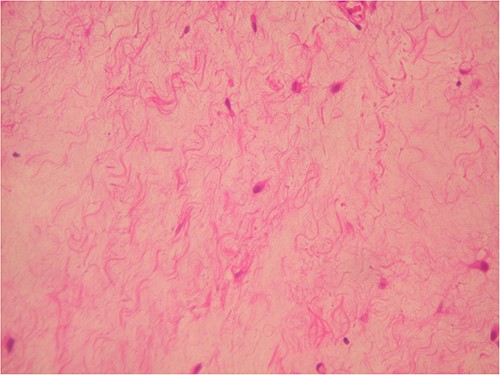

The surgically extracted in the toto mass was oval-shaped with a myxoid appearance, soft during palpation and yellowish in apperance. It was 3.2 cm at its greatest diameter. The mass was histologically and immunohistochemically examined (Figs 3–5). The tumor was severely hypocellular and consisted of stellate and spindle cells without atypia or mitosis, in an abundant myxoid stroma. Immunohistochemically, the tumor cells were positive for vimentin and CD34 but negative for SMA and S100. Based on these findings, a myxoma diagnosis was made.

Severe hypocellular tumors. Stellate and spindle cells in abundant myxoid stroma (H & E ×100).